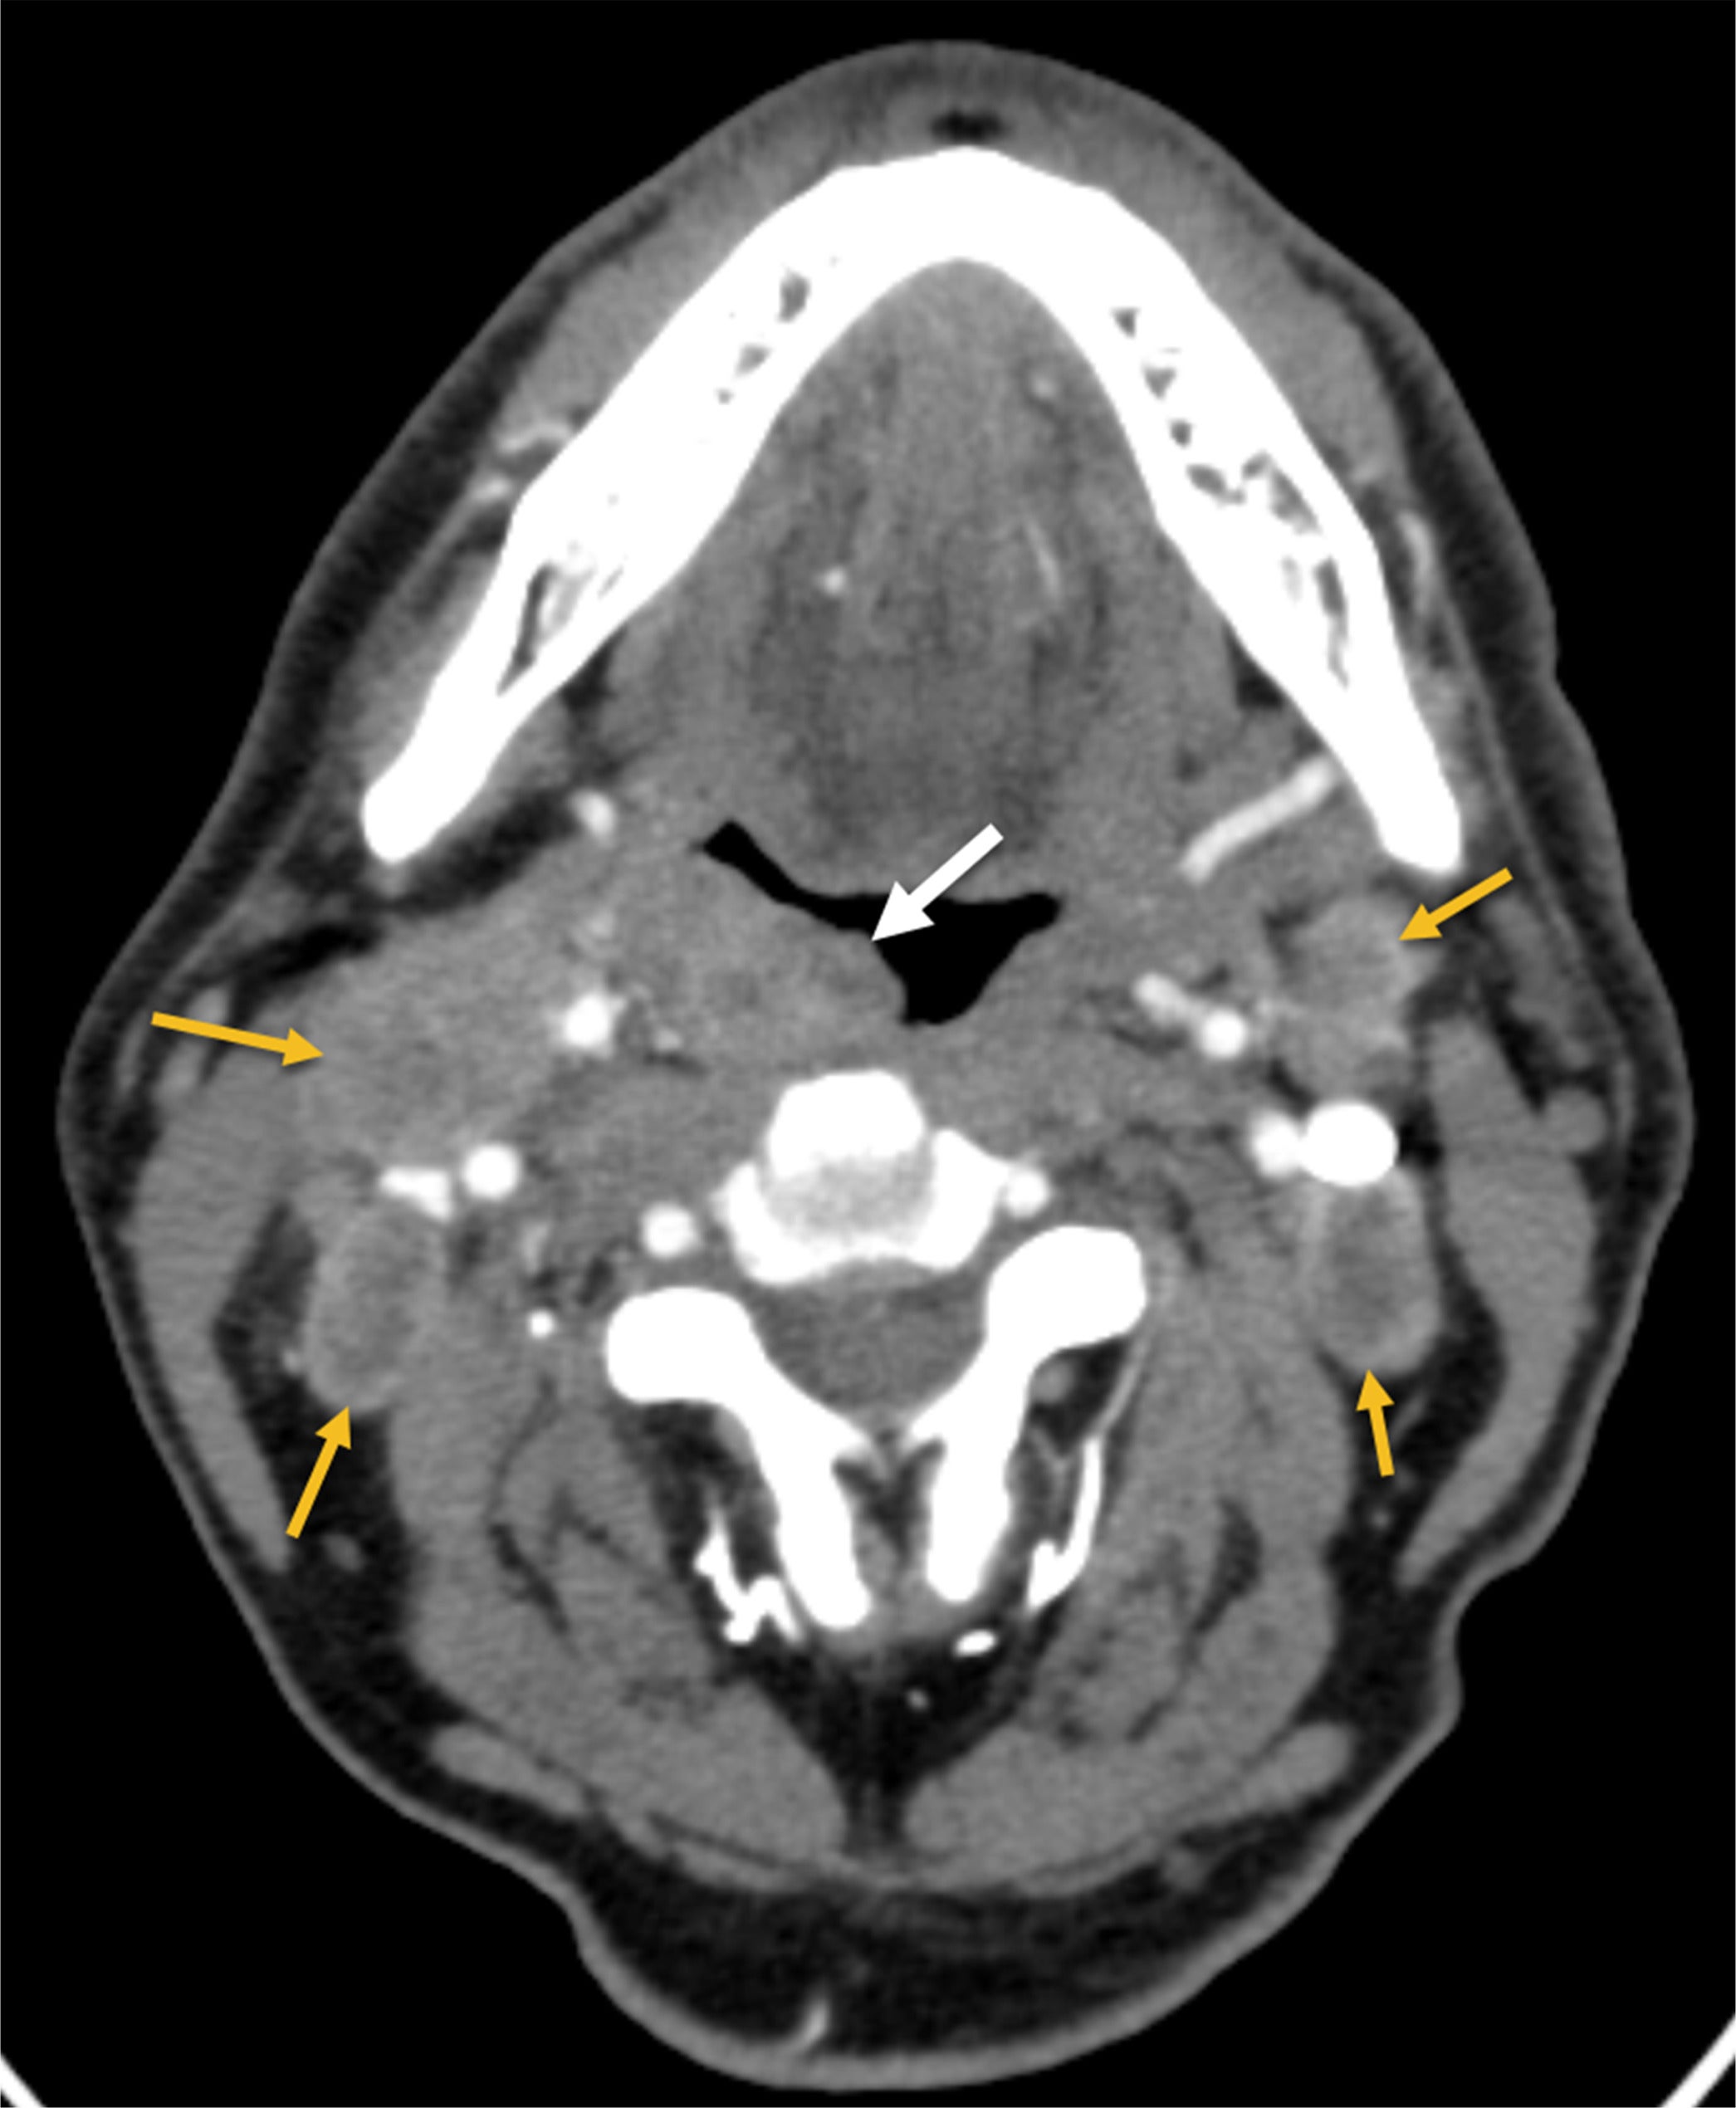

Contrast-enhanced CT of the neck ( Figure 1 ) demonstrated bilateral neck lymphadenopathy and a right palatine tonsil mass. Initial18 F fluorodeoxyglucose PET/CT scan ( Figure 2 ) demonstrated significant uptake in right palatine tonsil mass (Standardized Uptake Value (SUV) max 22) and bilateral neck lymph nodes (SUV max 11). The scan revealed no other FDG-avid masses specifically in the lungs. Following 4 cycles of cisplatin/etoposide chemotherapy and radiation therapy (60 Gy, Figure 2 ) and 5 months after the patient’s initial presentation, PET/CT demonstrated complete metabolic response with resolution of abnormal metabolism in right palatine tonsil mass and bilateral neck lymphadenopathy

CT scan of the neck with intravenous contrast demonstrates a right palatine tonsil mass (white arrow) and bilateral neck lymphadenopathy (yellow arrows).